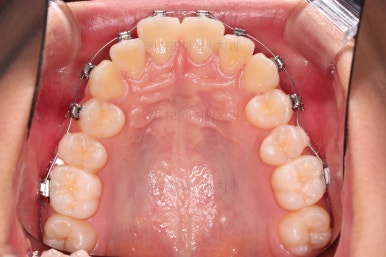

부산치아교정치과 키다리아저씨치과에서 마무리한 입안의 모습입니다.

가지런하게 잘 정렬이 되었고요.

윗니만 발치한 편악발치교정이지만 틈새 없이 공간이 닫혔으며 교합도 잘 맞습니다.

간혹 윗니만 발치를 해서 윗니만 갯수가 적어 교합에 문제가 되지 않나요? 라는 질문을 하시는 경우가 있는데요.

윗니 아랫니는 1:1로 대응 되는게 아니라 지그재그로 서로 엇갈려 있기 때문에 특히 윗니는 하나 모자라도 교합에 전혀 문제 되지 않습니다.

위아랫니가 가지런하게 보기 좋게 배열이 되었고요.

아랫니까지 윗니를 넣음으로써 튀어나와 보이던 앞니의 느낌이 좋아졌습니다.

물론 작은 아래턱에 맞춰 윗니를 뒤로 집어넣어야 해서 자칫 지나치게 들어간 입이 될까 염려되는 조심스러운 케이스였지만, 편악발치를 통해 최소한으로 입을 넣으면서 굉장히 조화롭게 잘 마무리 했습니다.